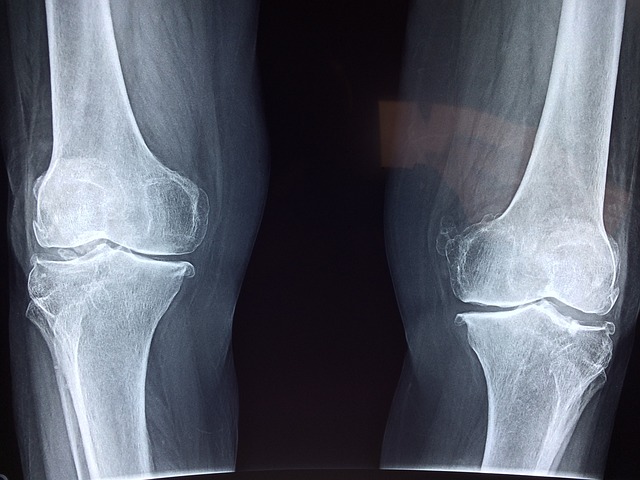

통풍은 관절이 아프고 붓는 질병입니다. 주로 발가락, 발목, 무릎 등 관절에 생기는 경우가 많고 급작스럽게 통증이 시작되어 당황스러워하시는 경우가 많습니다. 통풍은 요산이라는 것이 몸에 쌓여서 생기는 것인데 요산은 주로 음식을 통해 섭취하게 됩니다.

1. 심한 관절 통증: 통풍은 주로 엄지발가락 관절에서 시작되어, 발목, 무릎까지 통증을 일으키게 됩니다. 단 몇 시간 만에 통증이 극심해질 수 있습니다.

2. 관절 붓기 : 통증 부분이 붓고, 붉어지며, 뜨거워지는 느낌이 듭니다. 이로 인해 걷기가 힘들어집니다.

4. 만성 통풍 : 계속해서 재발하면 관절이 영구적으로 손상될 수 있습니다.